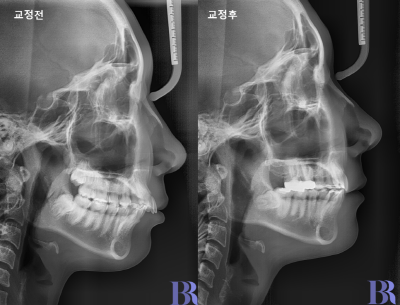

교정전후 옆모습 사진입니다.

입술라인이 과도하지 않고

자연스럽게 들어갔습니다

위 환자분 같은 경

아랫니까지 발치했다면

입술이 과하게 들어갔을겁니다.

교정 전후 옆모습입니다.

윗니와 아랫니 앞뒤 차이가

정상적으로 줄어들었고

교합도 긴밀하게 잘

맞는 것을 볼 수 있습니다.